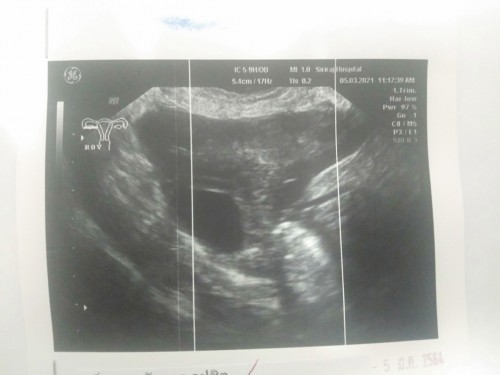

มีแม่ๆท่านไหนไปฝากท้องตอน4w+แล้วไม่เจอถุงตั้งครรภ์บ้างคะ แม่แอบกังวลและเครียดมากๆ

เราไปซาวครั้งแรกประมาน4วีค หมอก็บอกไม่เจอถุงตั้งครรภ์ อาจท้องนอกมดลูก เลยเว้นช่วงไปเดือนนึง พอซาวใหม่เจอน้องตอน9วีคคะ คุนแม่ไม่ต้องเครียดนะคะ

4w แม่ยังไม่เจออะไรเลยค่ะ เจอแค่ผนังมดลูกที่หนากว่าปกติน่าจะท้อง มาเห็นน้องพร้อมหัวใจตอน 8-9 w แม่ใจเย็นๆ นะคะ

เราไปฝาก 4 วีคค่ะ เจอแต่ถุงค่ะ หมอนัด 24/3 ไปใหม่ค่ะ รอลุ้นๆ

ถามค่ะ หมอว่าอาจจะมาฝากท้องเร็วไปหรือไม่อาจจะสาเหตุอื่น หมอนัดอีกทีศุกร์ที่19นี้ค่ะ ลุ้นมาก